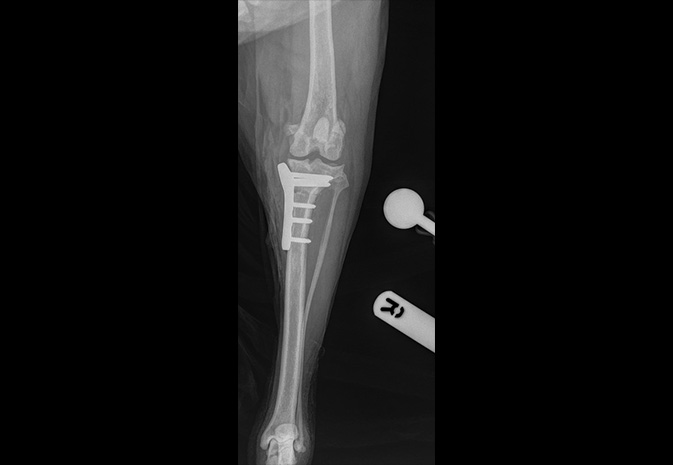

Fractures